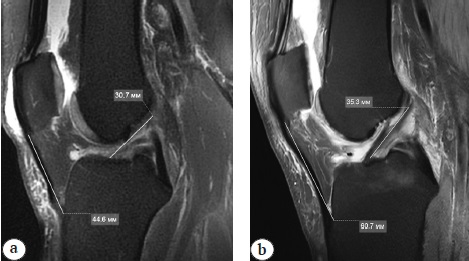

Рис. 1. Различные варианты длины связки надколенника: а — 44,6 мм; b — 60,7 мм

Fig. 1. The patella tendon length variation: a — 44.6 mm; b — 60.7 mm

Артроскопическая реконструкция передней крестообразной связки (ПКС) с использованием различных аутотрансплантатов признается большинством ортопедов золотым стандартом хирургического лечения при передней нестабильности коленного сустава [1, 2, 3]. При этом, несмотря на широкое применение сухожилий полусухожильной и нежной мышц (StG), использование средней трети связки надколенника с прилегающими костными блоками (BTB) в качестве аутотрансплантата ПКС сохраняет свою актуальность ввиду обеспечения плотной связи между костным блоком трансплантата и окружающей костью. Это позволяет начать реабилитационные мероприятия в раннем послеоперационном периоде и добиться полного восстановления функции сустава с возвращением пациентов в спорт в ранние сроки после операции [4]. В последнее десятилетие произошла смена парадигмы от транстибиальной методики рассверливания бедренного канала к рассверливанию последнего через переднемедиальный артроскопический порт. Такой подход позволяет добиться более анатомического расположения трасплантата и тем самым лучше обеспечить ротационную стабильность сустава [5, 6, 7]. В то же время использование данного трансплантата может быть сопряжено с избыточной длиной связки надколенника. Так, при средней длине ПКС 35,0 мм длина собственной связки надколенника варьирует от 40,0 до 60,0 мм (рис. 1).